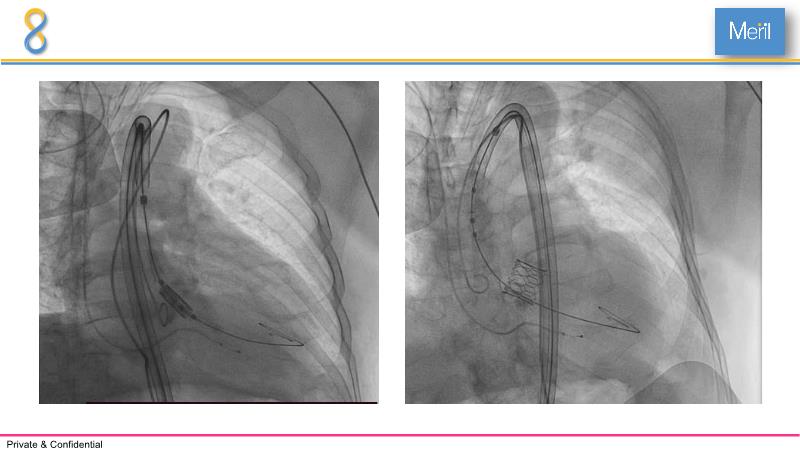

Through the presentation of several compelling cases, including an 88-year-old male with CKD, RBBB, moderate LV dysfunction, and severe aortic stenosis, a Type 1a bicuspid native AS, and an extraordinary TAVI in an 83-year-old with acute heart failure and comorbidities, this session will dive into the Myval Octapro THV. Learn about its key features, procedural impact, and potential clinical benefits. Discover the Octalign technique for predictable and precise commissural and coronary alignment, preserving coronary access. Gain insights into precise sizing, positioning, and deployment of the Myval THV series in real-world scenarios, and explore the relevance of pivotal Landmark RCTs in clinical practice.

- To know the Octalign technique which enables predictable and precise commissural and coronary alignment thus preserving coronary access